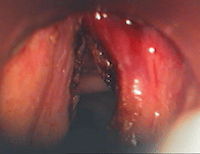

Dysphonie (altération de la voix) chez un patient tabagique: découverte d'une tumeur bénigne